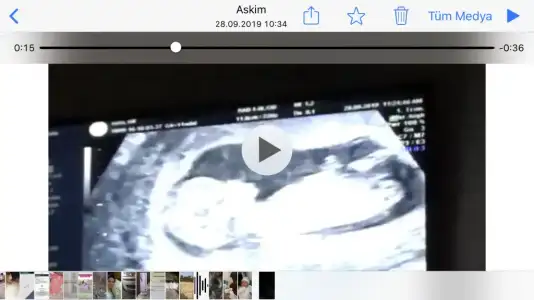

ErkekKızlar doktor çok erken dedi ama ben videoya çektim bugün burada nubu belli 11+0 bugün sizce nedir cinsiyet

Çok merak ediyorum ama doktor göremeditekrar gidecemBuda kuçük 11 yada 12 hafta olmalı

Bana kız gibi gelmişti ama insan merak etmeden duramıyor ya siz neresinden anladınız